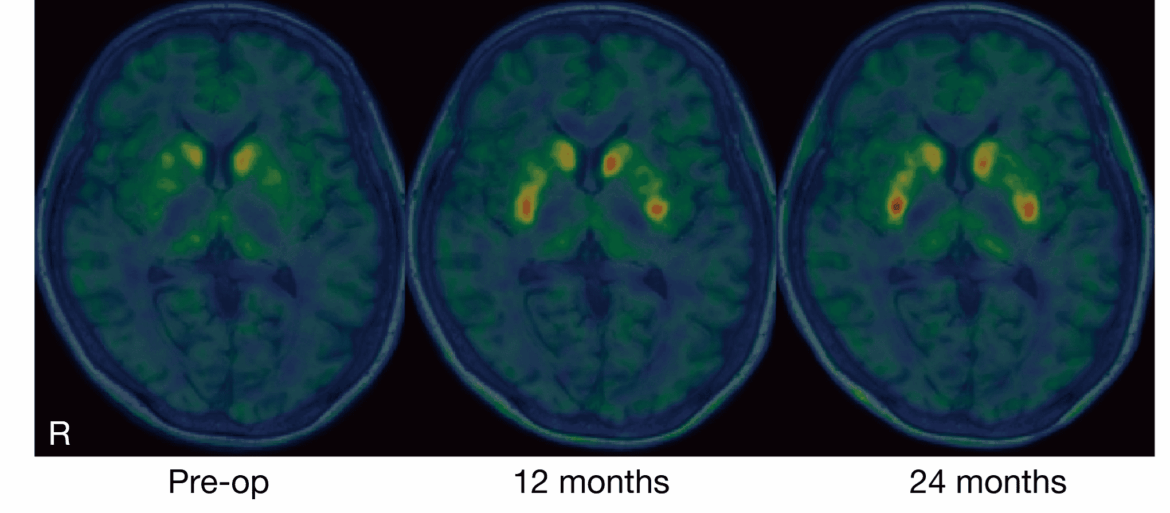

Changes before and after the procedure. Image from the study.

None of the patients had any major side effects and four showed improvements in movement when off their usual medications. Their average motor scores improved by 20%, and brain scans confirmed that the implanted cells were producing dopamine. A fifth patient improved while on medication. One patient didn’t improve, but their symptoms didn’t worsen either.

Researchers carried out brain scans to see how much dopamine production increased. They used a specialized tracer and found that in the patients that received the highest dose, dopamine increased by an average of 63.5%; in the low-dose group, it rose by just 7%.

Notably, in three patients, dopamine activity increased only in specific parts of the brain — right where the cells were injected. That local boost was still enough to improve symptoms in some cases, but there was no generalized return of dopamine production.